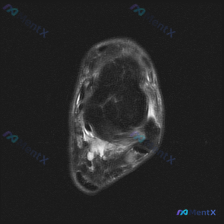

看到这个踝关节MRI的病例,整理了一下影像资料和分析思路,分享给大家讨论。 病例影像基本信息 本次提供的是踝关节水平MRI T2序列轴位图像,影像观察结果如下: 1. 骨骼结构:胫骨远端、腓骨远端、距骨穹窿骨皮质轮廓完整,无明显骨折线或显著骨髓信号异常 2. 踝关节间隙:可见少量液性信号,提示存在少...